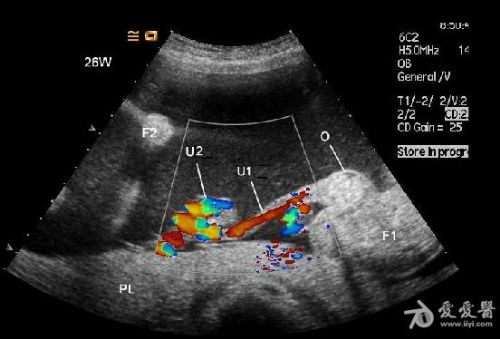

是双胎,其中畸形的那个明显没有上半身及头部,只有下半身和一点点短小的左上肢。

1.CDFI未见异常胎儿心脏显示,但胎体内可见血液流动。

6、频谱及彩色多普勒血流显像可显示无心畸胎脐动脉及脐静脉内血流方向与正常胎儿相反,无心畸胎脐动脉血流从胎盘流向胎儿髂内动脉达胎儿全身,脐静脉血流从胎儿脐部流向胎盘,正好与正常胎儿脐动脉、脐静脉血流方向相反。